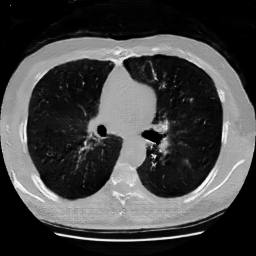

The study utilizes three 3D datasets, namely the GSP dataset[3], the LIDC-IDRI dataset[1], and the dataset employed for the Lung Nodule Analysis 2016 (LUNA16) challenge[21] which is a subset of LIDC-IDRI dataset. Samples from generated images at different stages of training are presented in Fig. 2 and Fig.3.

Figure 3: Synthetic images of CRF-GAN and HA-GAN at different iterations of training on the LUNA16 dataset